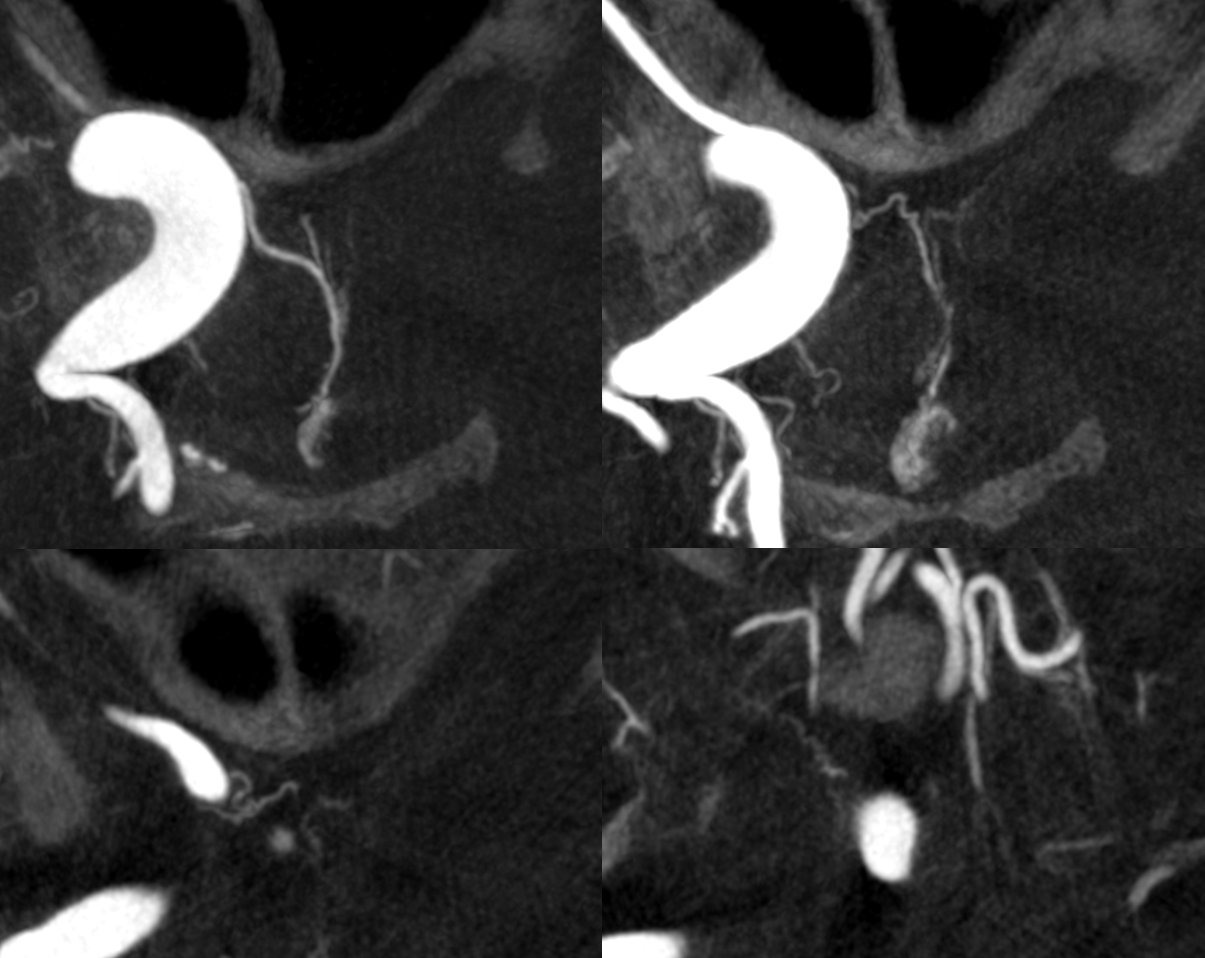

What supplies the bulk of optic nerve? Central Retinal artery is for the distal portion of nerve and retina. What about the rest — intracranial, intracanalicular, proximal intraconal segments? The answer is not clear (let me know if you do), but i believe the bulk of it comes from the superior hypophyseals. It is probably in balance with the recurrent branch of the central retinal artery. Below is an example of an especially prominent proximal-most superior hypophyseal (arrows) supplying the pituitary stalks and optic nerve in the canalicular and intracranial locations. Note how well one can see the branch in coronal view (bottom left image). In this case there are two large superior hypophyseals — the more distal one (dashed arrows) supplies predominantly the pituitary stalk. The inferior hypophyseal artery is marked by arrowhead. Lower right image is coronal.